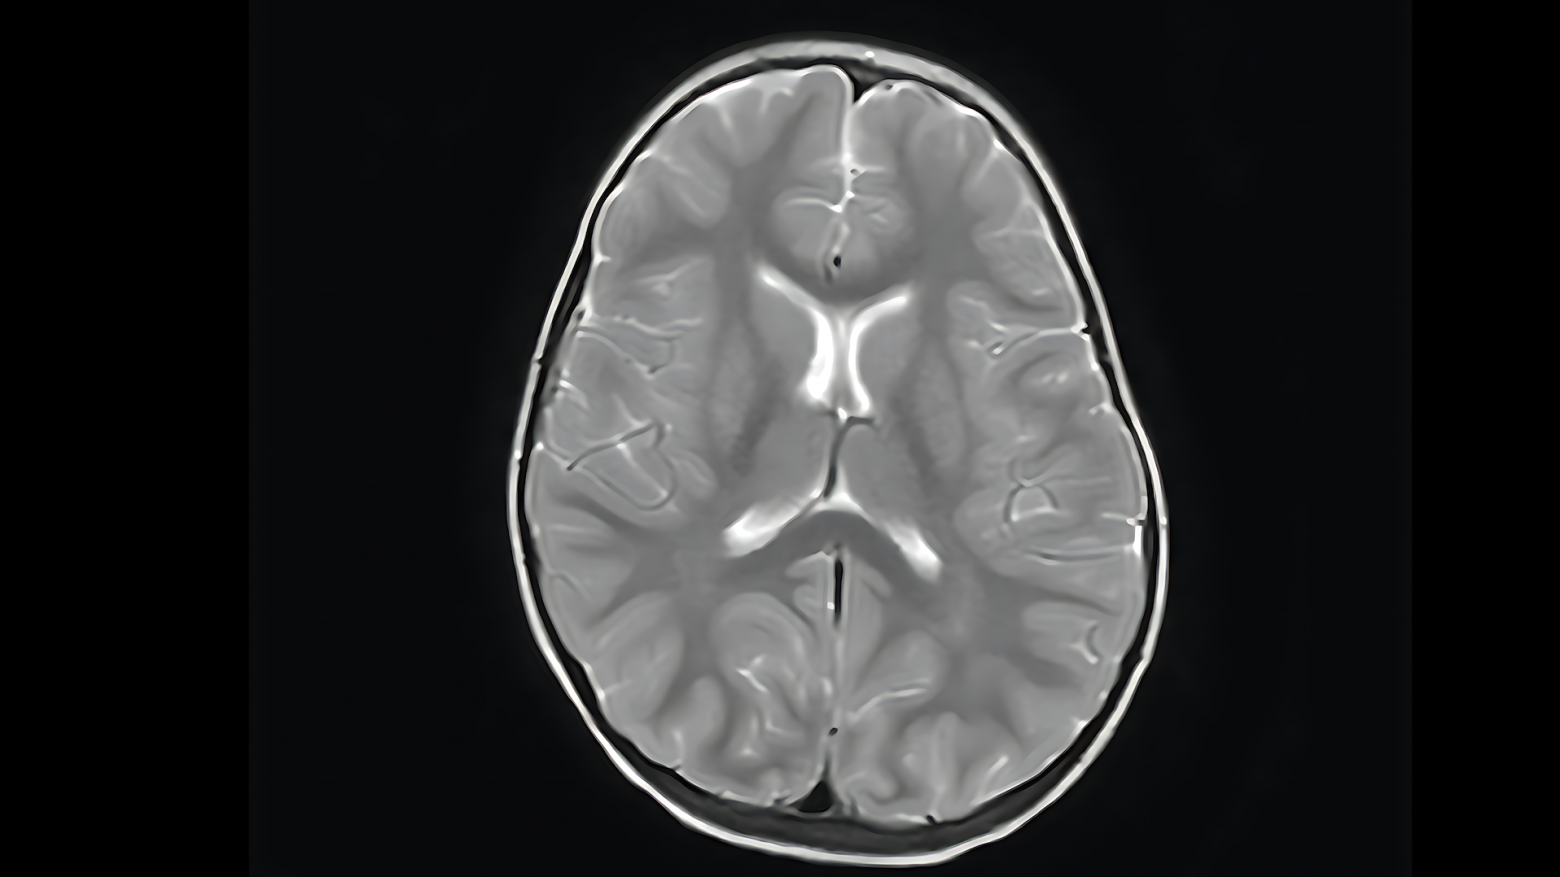

Вот как это работает на валидационной выборке. Исходное исследование из выборки:

Пример работы алгоритма: